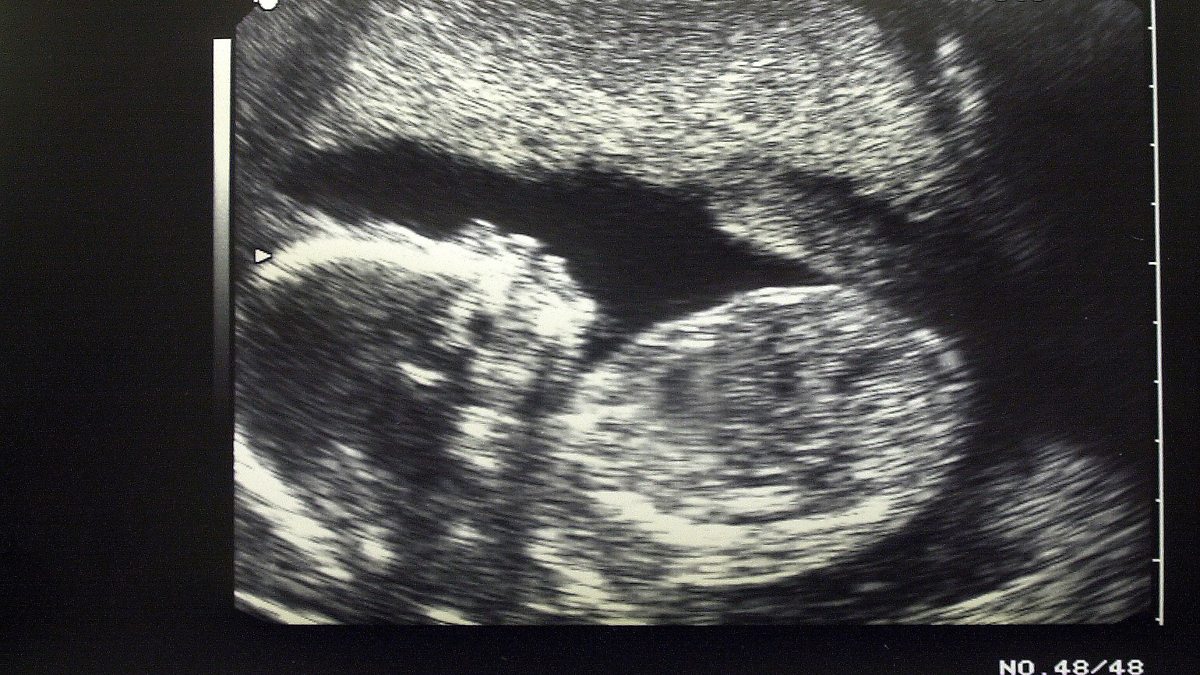

Surrogacy - dealing with Down's Syndrome

Amanda Benson spoke to Catrin Nye about dealing with Down's Syndrome in surrogacy